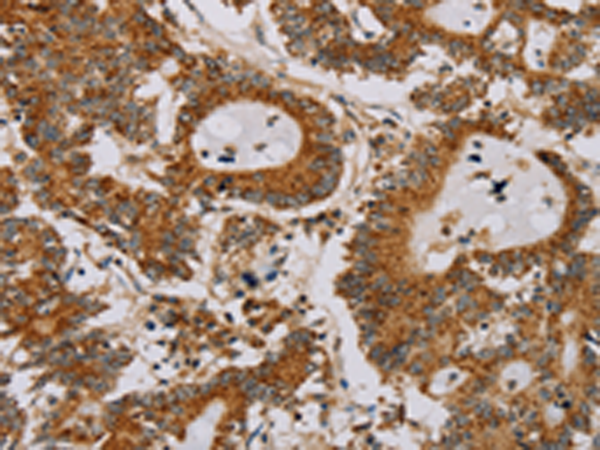

分类: 科研抗体货号: P08540别名: NOS2; ZC2HC12B应用: IHC反应种属: Human